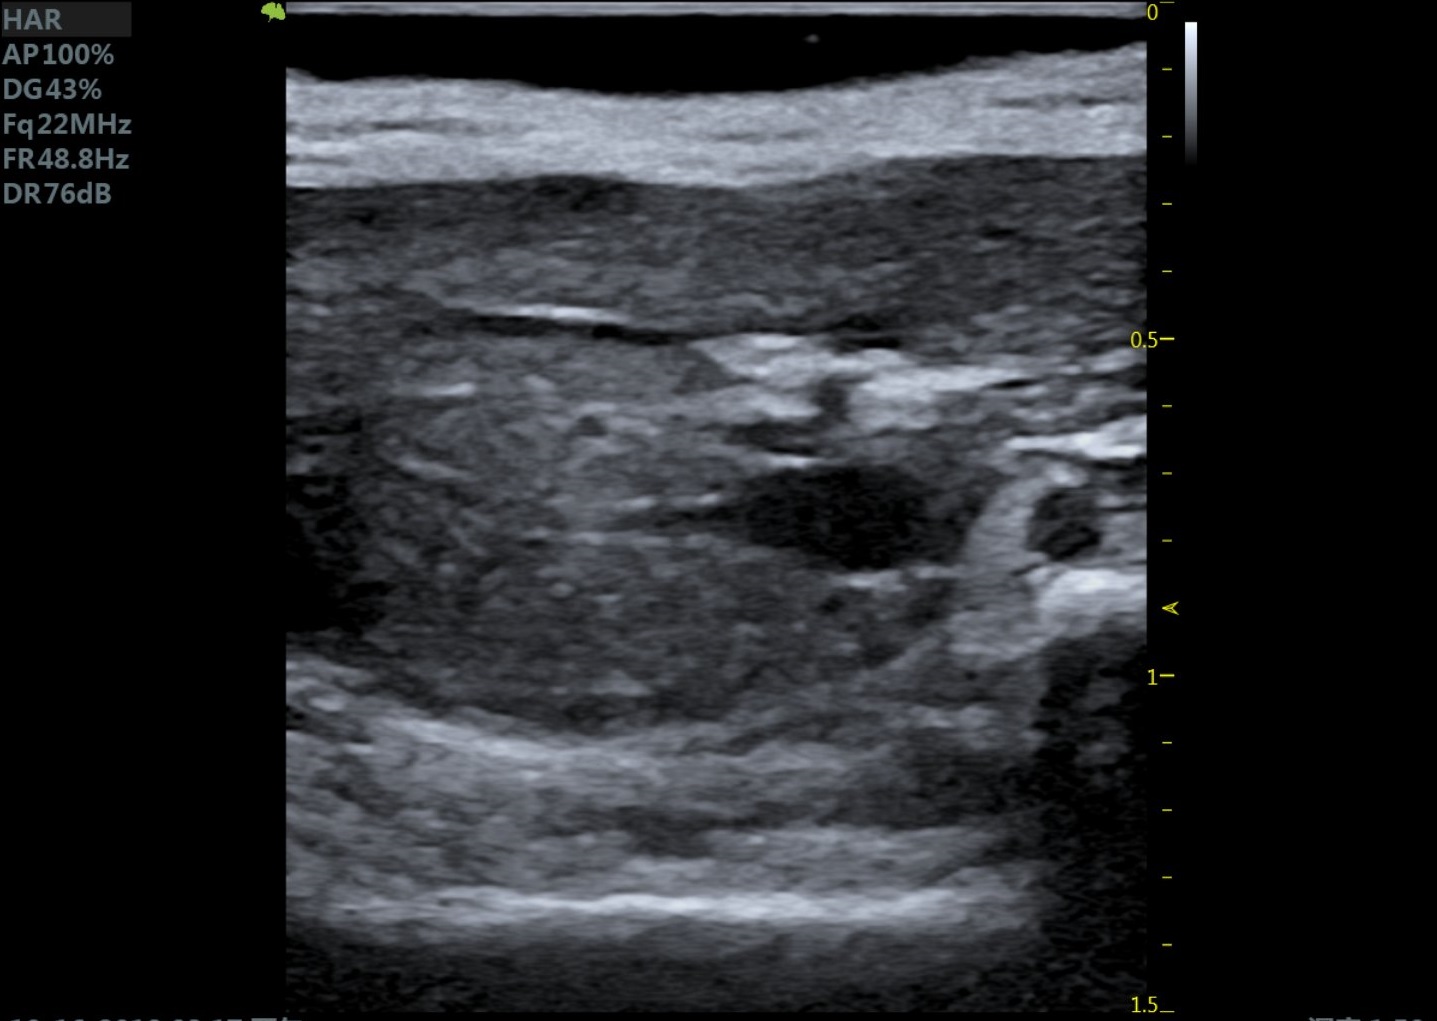

23MHz高频探头,优秀卓越的浅表显影

RF Flow充盈不外溢 Xcen超高频浅表显影

小鼠乳头肌水平 小鼠肝脏

大鼠肝脏 大鼠肾脏